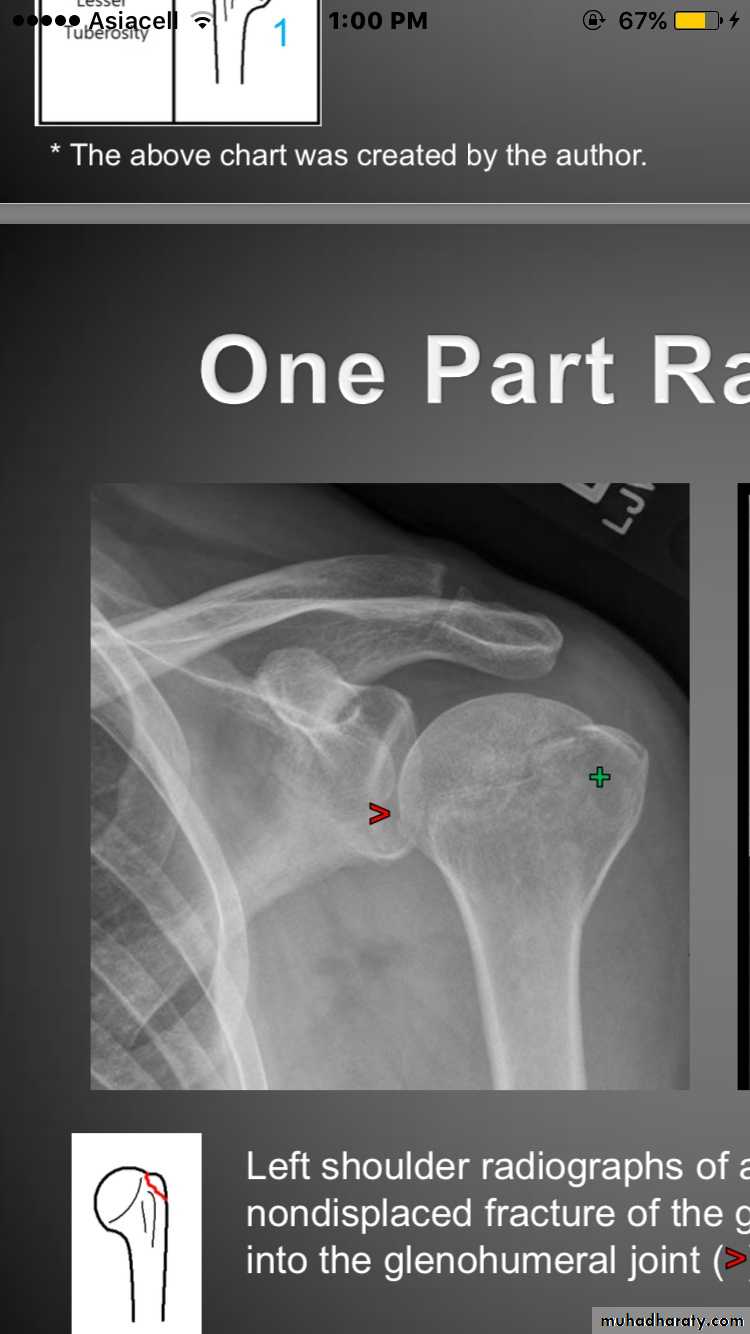

One _part fracture

Fracture lines involve 1-4partsNon of the parts are displaced (<1cm&<45degree)

70_80% of all proximal humeral fracture

8

X RAY